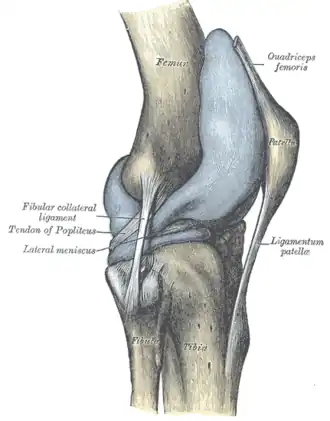

Lateral aspect of right knee -

Ligaments

The ligaments surrounding the knee joint offer stability by limiting movements and, together with the menisci and several bursae, protect the articular capsule.[19]

Intracapsular

The patellar ligament connects the patella to the tuberosity of the tibia. It is also occasionally called the patellar tendon because there is no definite separation between the quadriceps tendon (which surrounds the patella) and the area connecting the patella to the tibia.[23] This very strong ligament helps give the patella its mechanical leverage[24] and also functions as a cap for the condyles of the femur. Laterally and medially to the patellar ligament, the lateral and medial retinacula connect fibers from the vasti lateralis and medialis muscles to the tibia. Some fibers from the iliotibial tract radiate into the lateral retinaculum and the medial retinaculum receives some transverse fibers arising on the medial femoral epicondyle.[10]: 206

The medial collateral ligament (MCL a.k.a. "tibial") stretches from the medial epicondyle of the femur to the medial tibial condyle. It is composed of three groups of fibers, one stretching between the two bones, and two fused with the medial meniscus. The MCL is partly covered by the pes anserinus and the tendon of the semimembranosus passes under it.[10]: 206 It protects the medial side of the knee from being bent open by a stress applied to the lateral side of the knee (a valgus force).[10]: 206

The lateral collateral ligament (LCL a.k.a. "fibular") stretches from the lateral epicondyle of the femur to the head of fibula. It is separate from both the joint capsule and the lateral meniscus.[10]: 206 It protects the lateral side from an inside bending force (a varus force). The anterolateral ligament (ALL) is situated in front of the LCL.